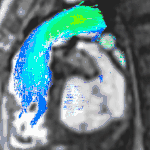

Partial Anomalous Pulmonary Venous Drainage by CMR